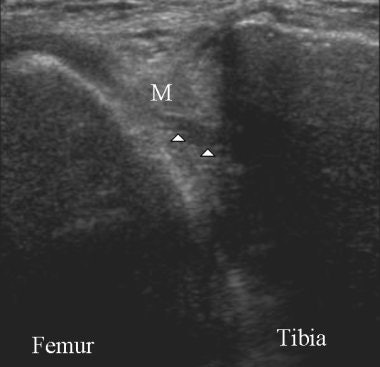

| Above, sagittal proton density-weighted MR image obtained through the posterior horn of the medial meniscus shows linear increased signal (arrow) extending to the inferior articular surface of the meniscus. Below, longitudinal ultrasonography obtained through the posterior horn of the medial meniscus shows a discrete hypoechoic cleft (arrowheads) extending to the tibial articular surface of the hyperechoic meniscus. Images courtesy of Dr. Gi-young Park. |